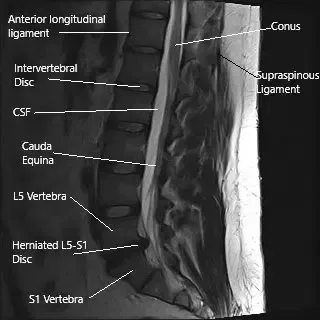

Resonancia magnética de la columna lumbar en la sección sagital que muestra una hernia del disco intervertebral L5-S1.

La columna vertebral está formada por vértebras separadas por discos intervertebrales, que amortiguan y estabilizan la columna. Las raíces nerviosas salen de la médula espinal a través del foramen intervertebral. La columna lumbar, en particular, es propensa a la hernia discal debido a su función de carga. El nervio ciático, que se origina en las raíces lumbar y sacra de la columna vertebral, recorre la pelvis y baja por las piernas, proporcionando funciones motoras y sensoriales.

¿Cómo encuentran el problema los médicos? (Diagnóstico e imagen)

El diagnóstico suele ser clínico, basado en la historia clínica y el examen físico del paciente. Las pruebas de imagen como la resonancia magnética son cruciales para identificar hernias discales, cambios degenerativos y otras anomalías estructurales en la columna lumbar. Las resonancias magnéticas en vistas sagital y axial proporcionan imágenes detalladas del espacio del disco, las raíces nerviosas y las estructuras circundantes, ayudando a guiar las decisiones de tratamiento.